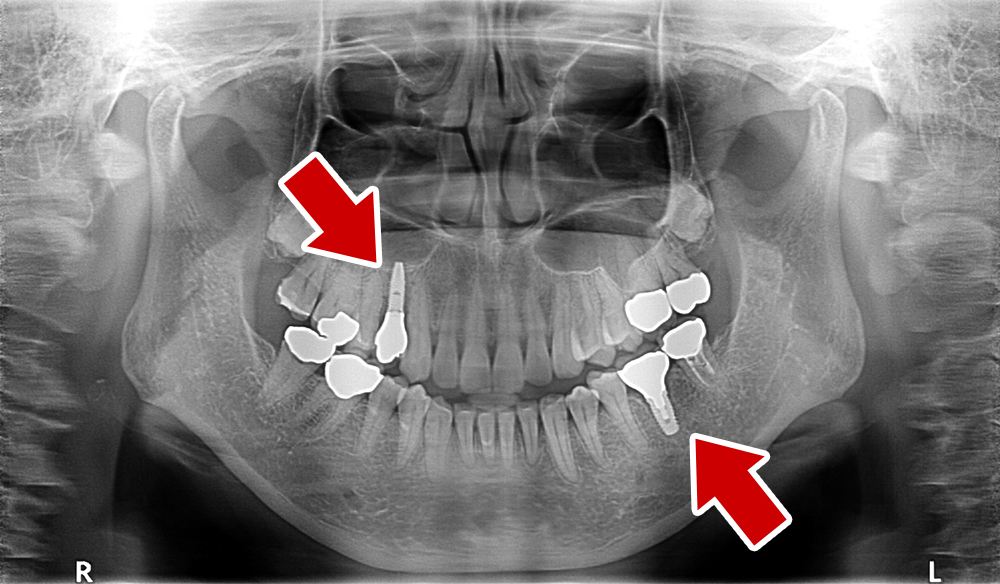

58歳 女性 歯科大学病院 教授からの紹介。

- 主訴

- 左下6番目、右上4番目の歯が長期にわたり痛く、噛めない、

- 処置内容

-

2本インプラント埋入+再生処置。抜歯即時埋入、⇒抜歯を行い、同時にインプラント埋入(即時埋入)

矯正処置

- 治療費用

- 上顎、下顎共に、約40万円(税込)(合計約80万円(税込))

- 治療期間

- 下顎:約6か月、上顎:約9か月

- リスク

- 上部構造物、仮歯の破折、術後の腫れ(3日)、人工歯根脱落リスクがあります

- その他

- 歯科大学病院 教授からの紹介。